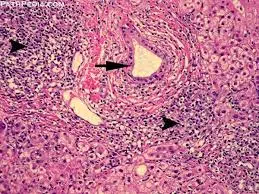

Autoimmune hepatitis is diagnosed with blood tests and a liver biopsy. During a liver biopsy, a small sample of liver tissue is removed with a needle and examined under a microscope.